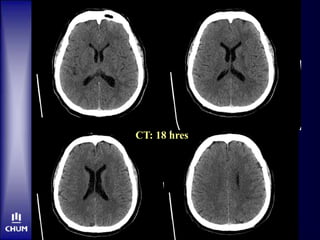

CT: 18 hres

M. N.  tPA-IV •OTTT: 3h15  Hyperglycémie malgré insuline IV  Aucune amélioration clinique